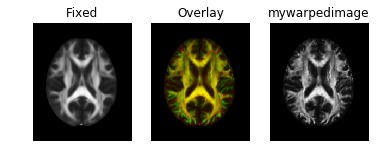

Results look good when visualized inside the same notebook. However, when I save the warped image to nifti file, it does not align in any other viewer. (I tried saving as ants image and also like this mywarpedimage.to_nibabel() but in all cases same results)

Here's how it looks: Fixed image:

Warped image:

Some sort of flipping. I tried changing the co-ordinate system of ants images as you can see commented lines in the code above. I tried using reorient_image2() function to have data in RAS before registration or even after registration. But in all cases, it gives me the same results.